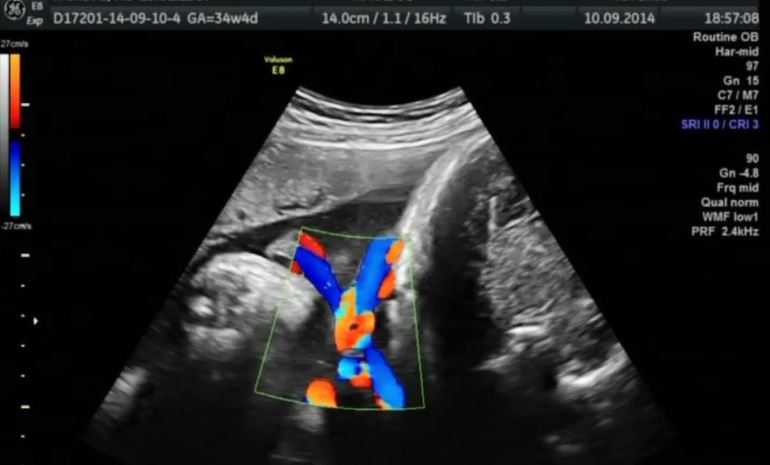

Ну и наше фото, как раз пуповина на шее подсвечена:

P.s. Вес 2450. Лежала личиком в спину, кроме уха и ручки нам ничего не продемонстрировала. Получается, личико мы так и не видели ни в 20, ни в 34, ну ничего - скоро познакомимся!